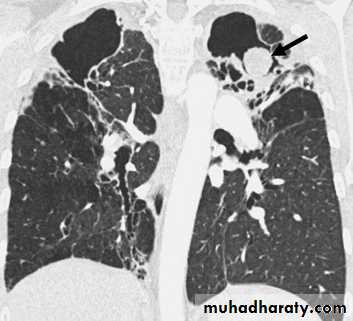

Plain film

* Tramline: horizontal, parallel lines corresponding to (cylindrical ) thickened, dilated bronchi

* Bronchial wall thickening (best seen end-on) as honey comb appearance ( cystic ) .

* Indistinctness of central vessels due to peribronchovascular inflammation

HRCT is more senstive , modality .of choice now adays

Signet ring sign : focally thickened bronchial wall adjacent to pulmonary artery branch .